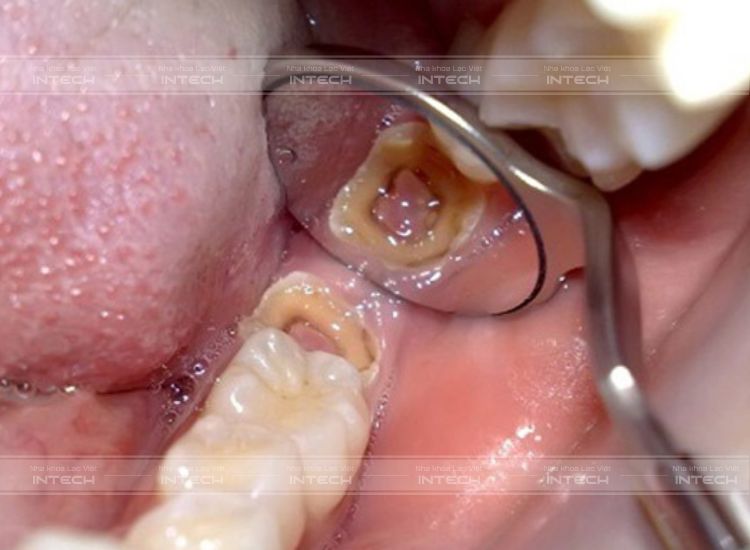

Nguyên nhân khiến răng số 8 sâu, vỡ

Sự chủ quan của người bệnh khi không điều trị triệt để trong giai đoạn đầu của sâu răng 8 là nguyên nhân chính dẫn đến chiếc răng này bị sâu, vỡ. Thời điểm này tạo ra môi trường thích hợp cho vi khuẩn xâm nhập, phát triển và sau đó ăn mòn chân răng.

Hiện tượng sâu răng 8Hiện tượng sâu răng 8

Bên cạnh đó, trong quá trình ăn uống, răng 8 phải chịu  một tác động lớn thì răng cũng dễ bị nứt và vỡ. Ngoài ra còn có một số nguyên nhân như sau gồm: